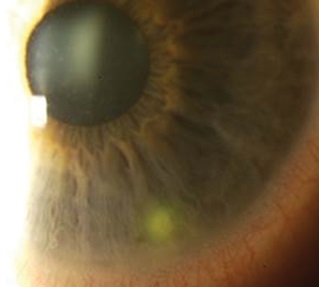

Acanthamoeba keratitis, almost exclusively seen in CL wearers, carries a much higher visual morbidity than bacterial CLMK and thus warrants special mention. The protozoan Acanthamoeba is ubiquitous in the environment, distributed in air, soil and water sources. The ability to transform into chemically resistant cysts in response to challenging environments allows Acanthamoeba to survive in chlorinated swimming pools and most CL multipurpose cleaning solutions4. Local data in Auckland show rising cases of Acanthamoeba keratitis peaking in the summer months from February to April5. Whether this suggests a climactic response in virulence or a higher rate of casual CL wear with high-risk behaviours has yet to be elucidated. Diagnostic delay is common, as the classic ring infiltrate with radial perineural infiltrates is only present in the late stages, whilst the early presentation of punctate epithelial erosion is commonly misdiagnosed as contact lens overwear (Fig 1). Other features overlapping with bacterial CLMK include stromal infiltrate (40%), anterior chamber reaction (29%) and epithelial defect (76%)5. Therefore, a high index of suspicion is required in all CLMK and begins with documentation of Acanthamoeba specific risk factors including hot-tub use, swimming and use of tank water supply5. Empirical therapy with antibiotics for bacterial CLMK usually leads to an initial improvement of symptoms (depleting the cornea of Acanthamoeba’s main nutritive source, bacteria), followed by a relapse once treatment is ceased.